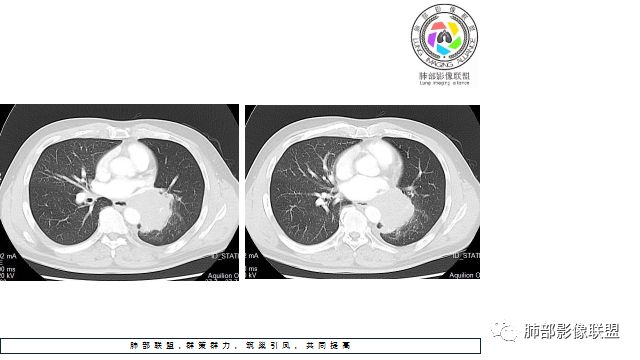

1.左下肺门区巨大肿块,支气管显示不清,轻度阻塞性炎症,没有明显肺不张,提示管腔受压狭窄可能性大于堵塞,这较少见于鳞癌。

2.病灶边缘光滑,未见明显分叶、毛刺,未见明显强化,这符合腺癌影像学特点,却符合神经内分泌癌表现。

3.病灶内密度均匀,轻到中度均匀强化,大病灶未见明显液化坏死区及空洞,不符合鳞癌而符合小细胞肺癌特点。

4.病灶内有肺动脉走形,血管局部受压,未见破坏,病灶乏血供,呈血管包埋或血管造影征;侵袭性力强及破坏力弱、血管漂浮都符合SCLC,所以鳞癌的可能性也不大。

5.左肺门块影或淋巴结肿大,竭力挤兑肺门血管结构,呈冰冻肺门;有时候SCLC可以单独呈现冰冻肺门,而没有没有冰冻纵隔。